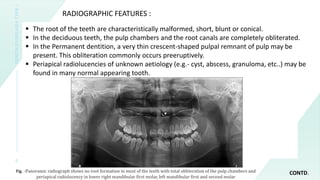

Das initial gebildete Dentin ist normal, beim Typ I findet sich in der obliterierten Pulpa atypische knollenartige Hartsubstanz. Bei bleibenden Zähnen kann ein halbmondförmiger Rest der Pulpa auf Höhe der Schmelz-Zement-Grenze bestehen bleiben. Beim Typ II ist die Pulpa distelartig und nicht vollständig obliteriert. Die Wurzel ist normal lang, aber dünner.

Typ I hat Zähne ohne oder mit spitzen konischen Wurzeln. Es kommt häufig zu vorzeitigem Zahnverlust.

Typ II hat Zähne mit normalen Wurzeln, einer bernsteinartigen Verfärbung der Milchzähne. Die bleibenden Zähne sind nicht oder nur gering verändert. Es treten vermehrt Knochenläsionen der Alveolarfortsätze auf.

Die Diagnose ergibt sich aus der zahnärztlichen Untersuchung einschließlich der Orthopantomographie.